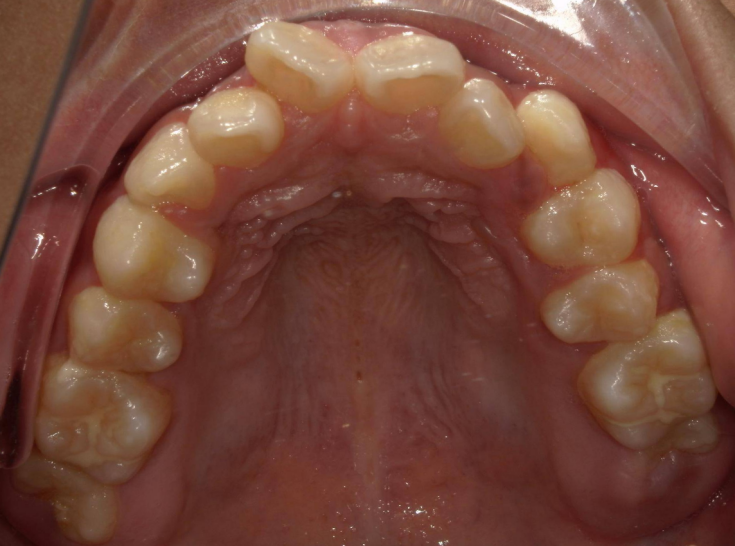

我们的颌骨就像一栋“牙齿公寓”,每颗牙齿都需要固定的“居住面积”。但由于遗传、发育等因素,不少人的“公寓”面积先天不足:颌骨长度或宽度不够,而牙齿的数量和大小却没减少。这就会导致牙齿挤在狭小的空间里,出现拥挤不齐(比如牙齿重叠、扭转)、门牙前突(嘴唇闭不上、侧面看嘴型突出)等问题。

这是最常见的需求。中度以上的牙齿拥挤(比如拥挤度>4mm),单纯靠扩弓(扩大牙弓宽度)往往无法获得足够空间,强行排列可能导致牙齿受力过大、牙根吸收,甚至变成整齐的龅牙。此时拔牙(多为智齿、双尖牙,可被替代功能的牙齿),能快速释放空间,让拥挤的牙齿顺利排齐,同时保证每颗牙齿的排列角度、间距都符合生理标准。